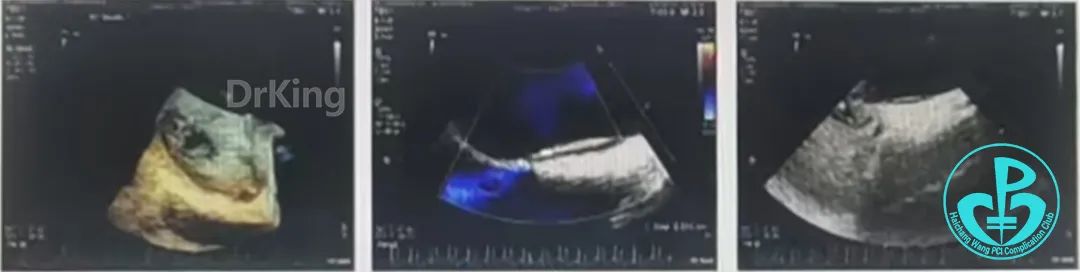

经食道超声三维、二维和右心声学造影图像: